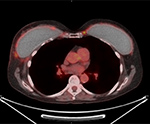

55 year-old woman with history of breast cancer status post bilateral mastectomies and implants. Axial CT (A), FDG PET (B), fused PET-CT (C), and MIP (D) images demonstrate smooth thin rim of FDG activity around the breast implants bilaterally representing peri-implant inflammation. |

| 55 year-old woman with history of breast cancer status post bilateral mastectomies and implants. Axial CT (A), FDG PET (B), fused PET-CT (C), and MIP (D) images demonstrate smooth thin rim of FDG activity around the breast implants bilaterally representing peri-implant inflammation. |